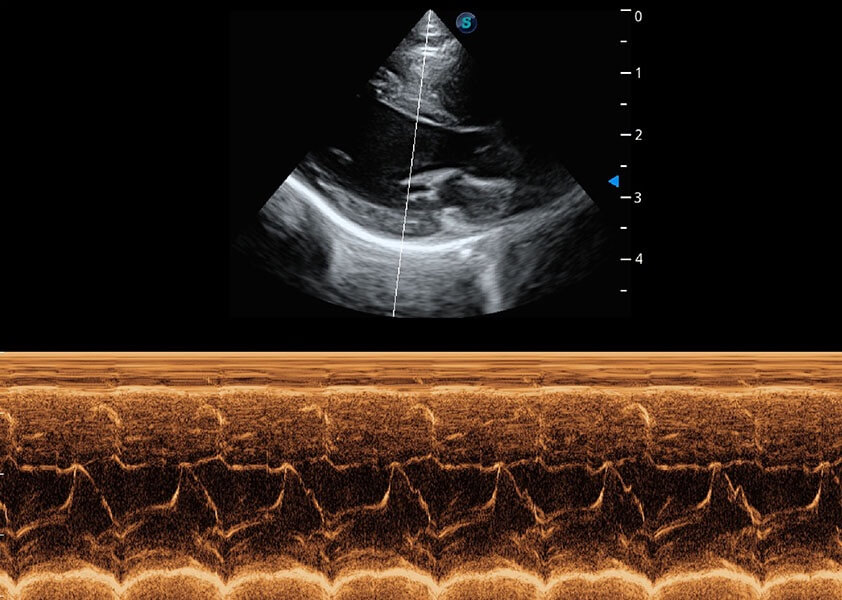

ProPet 60 作为一款高端台式动物超声设备,为动物医生的日常诊断提供了一系列贴合动物临床需求、解决临床实际问题的高级成像功能。凭借全系列高清探头,满足医生对腹部、心脏、生殖、浅表、肌骨等成像的所有需求,切实帮助您提升检查效率,提高诊断信心。

动物是人类最亲密的朋友和最值得信赖的伙伴。哈哈体育官网也一直致力于探索动物专用的超声影像解决方案。 全新推出的ProPet系列,是哈哈体育官网在动物超声影像智能化、专业化、精准化的一次跨越式革新。动物不能用言语来表述自己的不适,通过超声影像,ProPet系列搭建了动物医生与不同物种沟通的“桥梁”,为动物医生注入了“治愈之力”。